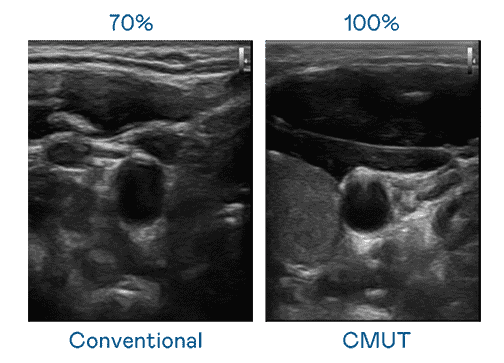

CMUT 技术是一种用电容式微机电元件来产生超音波讯号的技术。。与传统 PZT 压电式技术相比,,CMUT 频宽增加 30%,,,,更宽频的超音波讯号让影像解析度大幅提升,,,是实现高影像品质医疗超音波扫描、、促进精准医疗发展的关键技术。。

大频宽带来超清晰影像

超音波影像的解析度高低,,首先取决于探头能发出的讯号频宽。。。。PG国际 CMUT 可提供高清晰的超音波讯号,,,提供高频宽、、、高灵敏度、、影像纹理细节更高的超音波影像,,,,协助医护人员缩短影像判读时间及利用精准的医疗影像进行诊断。。